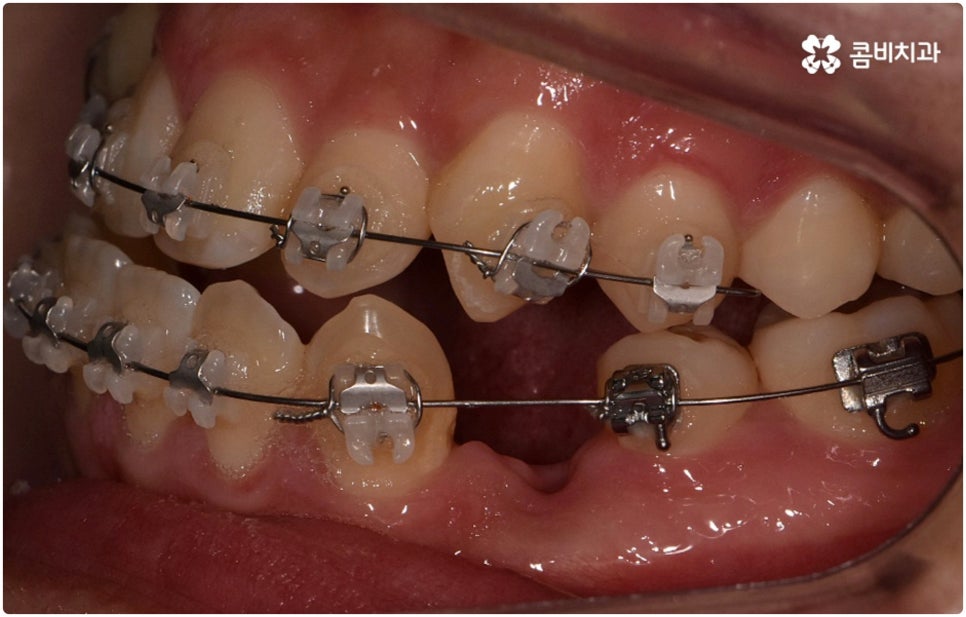

환자분들마다 상황은 모두 다르기 때문에 부정교합 교정 치료를 할 때는 정밀 검진 후 맞춤 치료 계획에 따라 무리하지 않게 진행하는 것이 중요한 포인트라고 할 수 있어요. 이때 구강내 상태 (치아, 잇몸, 치열, 교합 등) 뿐 아니라 구강 외 상태 (뼈의 위치 및 구조 발달, 얼굴 정면과 측면 등 안모 비율) 와 같은 모든 부분을 꼼꼼하게 촬영하고 환자의 연령 및 생활 습관 등을 종합적으로 고려하여 원인을 분석한 다음 치아를 어떻게 얼마나 움직여야할지 면밀하게 교정 플랜을 세우는 것이 필요하므로 3D CT, 모르페우스 같은 정밀 진단 기계를 갖추고 있는 치과에서 다양한 임상 경험을 통해 뛰어난 기술력을 가지고 있는 담당의 선생님께 치료 받으시길 권유드리고 있습니다.

하지만 관련 기술 발달로 교정에 있어서 적기라는 것이 크게 의미가 없어진 근래에는 정도가 많이 심각하지 않다면 중장년 성인분들의 경우에도 각자에게 맞는 교정 치료를 통해서 얼마든지 부정교합 개선이 가능하니 안될 것이라고 지레 짐작을 하여 내원을 망설이시기 보다는 먼저 교정 치료를 위한 검진을 받아보고 자신의 상황에 대해서 숙련된 의료진과 충분히 상담해 보시길 권유드리고 있습니다. 특히 수술적인 치료를 할 때도 교합을 바로잡기 위해서는 치과와 협진하여 진행하는 케이스가 많으니 교정을 통한 부정교합 개선 및 턱관절 치료 효과에 대해 크게 의구심을 가지실 필요는 없을 거예요. 상황에 따라 교정 치료만으로도 기능적 개선은 물론 균형잡힌 안모와 호감가는 인상으로의 변화가 가능한 경우가 많으니 불편함을 참고 계시지 말고 정밀 진단과 상담부터 차근차근 시작해 보시면 필요한 도움을 받아 보실 수 있어요.